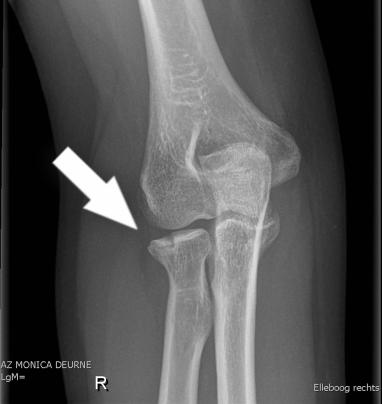

What is it?

The radial head and neck are parts of the bones in the elbow. Fractures typically occur due to a fall onto an outstretched hand. If the fracture is very displaced, then some people need to have surgery to correct this and allow the bone to heal in a better position.